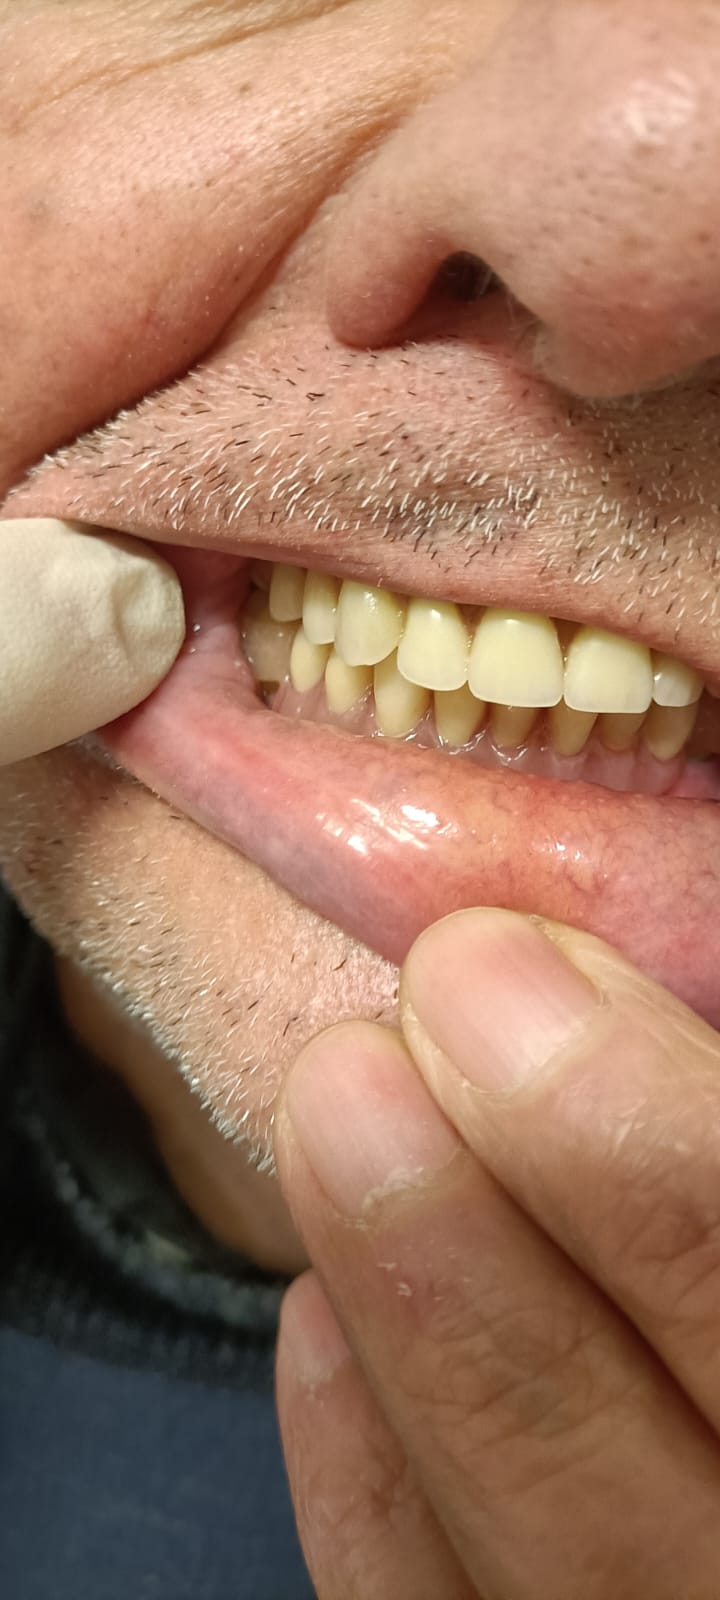

Workflow e Casi Clinici - Protesi Dentarie Realizzate

Successi Clinici - Laboratorio Odontotecnico Torino Piemonte

La sinergia tra tecnico e clinico garantisce la piena soddisfazione del paziente finale.